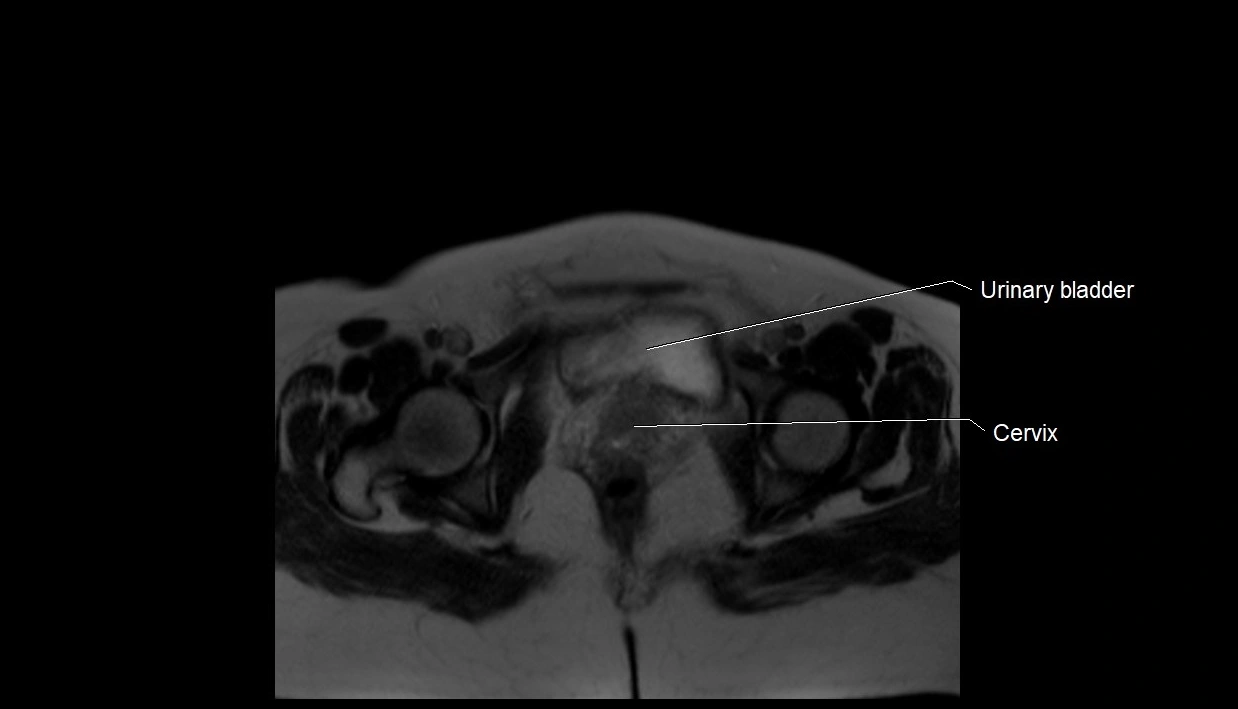

MRI Appearance

T2 HASTE (T2 GRE):

• Amniotic fluid shows very bright hyperintense signal

• Provides natural contrast against fetus and placenta

• Small particles (vernix) may appear as scattered hypointense foci within bright fluid

T1 GRE:

• Amniotic fluid shows low signal intensity (dark)

• Hemorrhage, infection, or proteinaceous content may cause focal or diffuse high signal intensity

MRI image

image